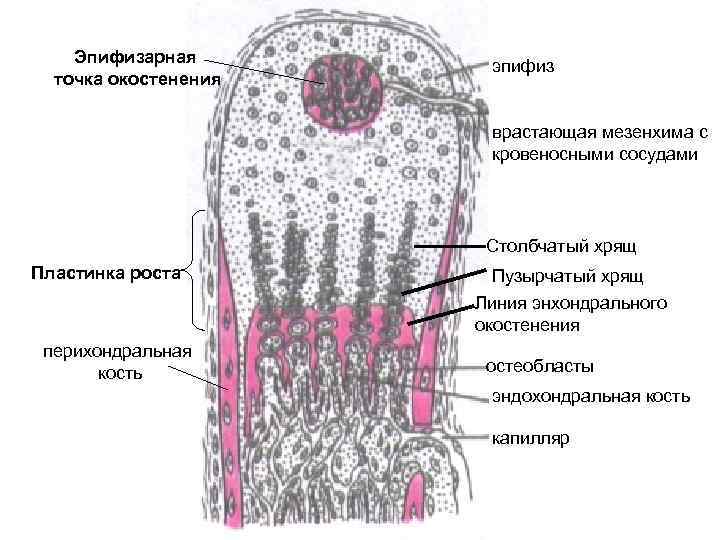

Структура грубоволокнистой костной ткани: наглядные примеры